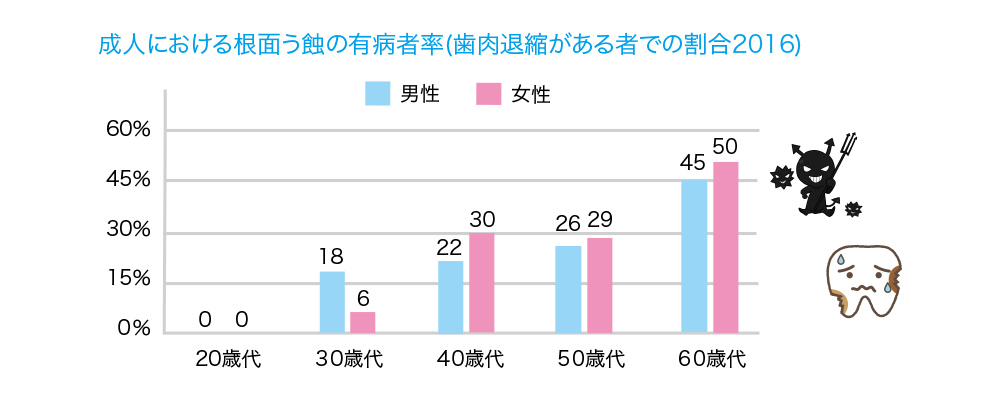

根面う蝕のリスクは40代で急激に高まり、以降、加齢にともなってリスクがより高くなります。東京歯科大学・杉原直樹教授らによる2016年の報告では、根面う蝕の有病率は歯肉退縮がある方で、20代では0%ですが、30代から発症が見られ、40代で約20~30%、50代で約30%、60代では約45~50%でした。根面う蝕は、30代からリスクがあるため、大人も早めからのケアが大切です。